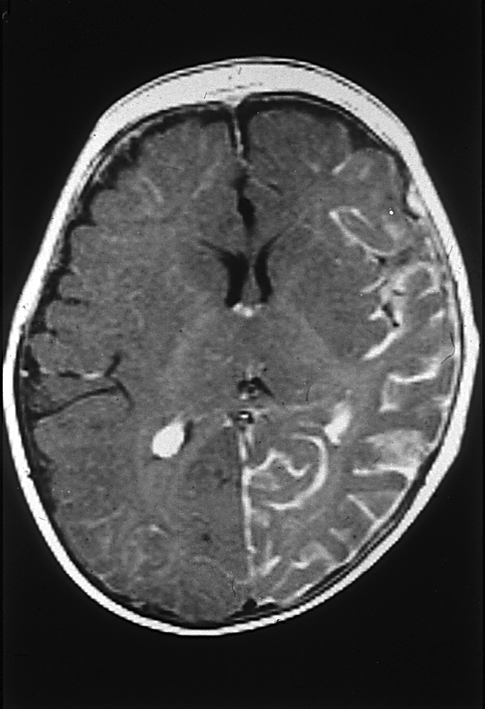

Additionally, in certain instances, a paediatric neurologist may recommend further imaging studies known as MR angiography (MRA) and MR venography (MRV). These tests provide a comprehensive evaluation of the arteries and veins within the head, offering vital insights that can aid in diagnosis and treatment planning.